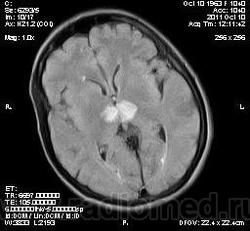

женщина 1963 года рождения. давность заболевания 10 дней.

Билатеральный таламический инфаркт. Либо венозный, либо вследствие закупорки одной из ветвей задней мозговой артерии - ЗМА (вариан развития ЗМА). Но не средней мозговой артерии (СМА). Мне представляеться, что здесь второе... За венозный инфаркт данных не вижу.

Может не как следствие закупорки сосуда, а гемодинамический инфаркт в ВББ (таламо-субталомических ветвей ЗМА)?

MELAS? Чем черт не шутит?

MELAS- по лаколизации очень похоже, но пока нет достоверных данных на него указывающих